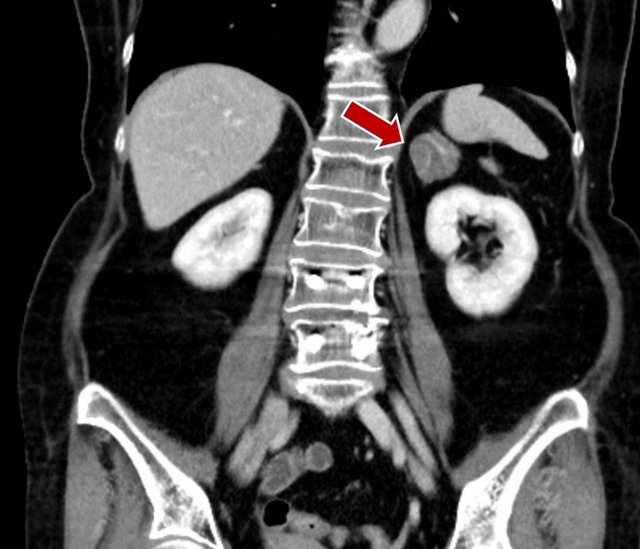

63歲張女士近半年飲食正常,體重卻快速增加,除腰部衣服變緊、臉變圓外,小腿肌肉量也大幅減少,走不遠就腳痠需要休息,且常有高血壓、頭痛、失眠、疲倦無力等病症,趕緊就醫。經心臟血管科及新陳代謝科診斷,排除腦下垂體疾病後,安排電腦斷層檢查,發現其右側腎上腺有顆3.6公分的腫瘤,確診罹患較罕見的「庫欣氏症」。

許竣凱說,治療庫欣氏症的最終目的是減少皮質醇過多之問題,臨床醫師會先詢問病人是否有在服用藥物,排除外源性因素後,經尿液、血液、電腦斷層等系列檢查,確認病因是腎上腺腫瘤引起,而後交由泌尿科醫師切除腫瘤。術後醫師會開立類固醇藥物,以利壓力荷爾蒙之控制,而後病人只要熬過約3個月的適應期症狀(如腸胃不舒服等),半年內即可恢復過往狀態。